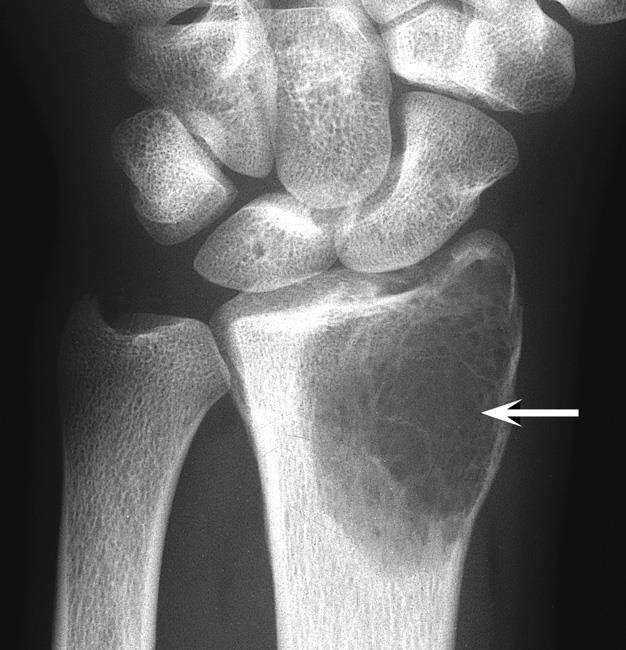

संग्रह 2021: जाइंट सेल ट्यूमर एक्स रे

यहां आपको वह मिलेगा जिसकी आपको तलाश थी - जाइंट सेल ट्यूमर एक्स रे

X Ray Multiple Part Of Child S Body Multiple Disease Stroke Brain Tumor Rheumatoid Arthritis Sinusitis Gouty Arthritis Etc Skull Chest Lung Heart Spine Arm Hand